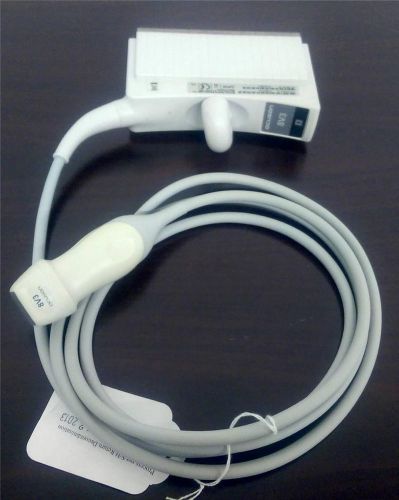

Acuson 15L8w Transducer Probe Breast 8 to 15 MHZ Sequoia Ultrasound WARRANTY #2